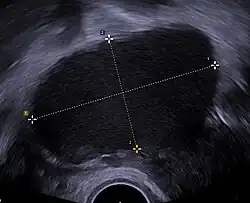

A health history and a physical examination can lead the health care practitioner to suspect endometriosis. There is a clear benefit for performing a transvaginal ultrasound (TVUS) as a first step of testing for endometriosis.[97]

Ultrasound

Vaginal ultrasound can be used to diagnose endometriosis or to localize an endometrioma before surgery.[112] This can be used to identify the spread of disease in individuals with well-established clinical suspicion of endometriosis.[112] Vaginal ultrasound is inexpensive, easily accessible, has no contraindications, and requires no preparation.[112] By extending the ultrasound assessment into the posterior and anterior pelvic compartments, a sonographer can evaluate structural mobility and look for deep infiltrating endometriotic nodules.[113] Better sonographic detection of deep infiltrating endometriosis could reduce the number of diagnostic laparoscopies, as well as guide disease management and enhance patient quality of life.[113]